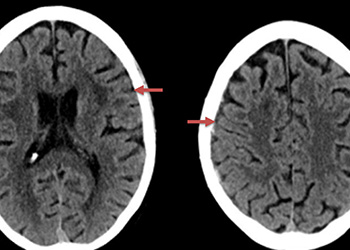

Brain:

Neurosurgeons Collaborate to Treat Giant Symptomatic Meningioma

Author: Ramin Rak M.D., F.A.A.N.S., F.C.N.S., Jonathan L. Brisman M.D., F.A.C.S., Read More!